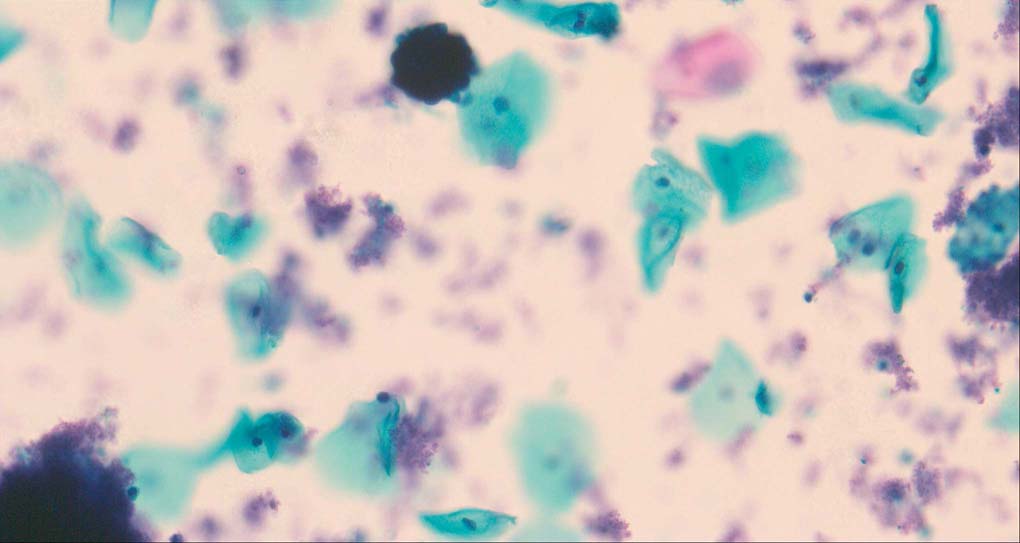

A good image fusion method should contain the following properties. First, it preserves both the details of small size objects and the integrity information of large size objects in the fused image, even in the case of the size of the interested objects varying largely in the image. For example, the cervical cell images from the microscope contain both small size isolated cells and large size agglomerates, which are both useful for cervical cytology [5]. Second, it should be efficient enough to handle large-scale data. For instance, it needs to process thousands of fields of view (FoV) in an acceptable time for the whole slide scanning in digital cytopathology [6], which requires to fuse a series of high resolution images captured at each FoV in a very efficient way. Third, it does not produce obvious artifacts. Despite being studied extensively, to our best knowledge, existing fusion methods may not meet these requirements simultaneously.

To demonstrate the effectiveness and efficiency of the proposed image fusion method , we conduct a set of comparative experiments on three image datasets. The first is composed by 8 pairs of multi-modal medical images and the second one contains 15 pairs of multi-focus gray or color natural images. These two datasets are often used in many related papers and some examples are shown in Figure 3(a) and Figure 3(b). The third one is a new multi-focus cervical cell image dataset collected by ourselves, which consists of 15 groups of color images and each group contains a series of multi-focus cervix cell images with size of or , etc. Some source examples are shown in Figure 3(c). Our source code implemented in C++ along with the new multi-focus cervical cell image dataset is available online.

Figure 9, Figure 10 and Figure 11 show the comparative fused results of the multi-focus cell images shown in Figure 3(c). For clarity, we also present a closeup view in the right-bottom of each sub-picture in Figure 9 and Figure 10. As shown in the close-up views of Figure 9, the fused images based on DSIFT, IM, MWGF and BF methods are extremely blurred in the boundary and fail to keep the details of cell nucleus. Furthermore, the DTCWT and NSCT based methods produce halo artifacts in the fused images, while GFF and CNN based methods fail to preserve the small cell nucleus. LP-SR based method nearly works fine which keeps the most of the details of the small size cells, but the integrity of the clustered large size cells is damaged. Fortunately, in our proposed method, the integrity of the clustered large size cells is preserved and most of the isolated small size cells are maintained from the original images, which demonstrates the best visual quality.

Similarly, as shown in the close-up views of Figure 10, the fused images from DSIFT, IM, MWGF and BF are blurred and lose some nucleus details, while the results from DTCWT, GFF, CNN and NSCT produce halo artifacts. LP-SR based method can keep details well but also produces halo artifacts and other noise. Our method can preserve the focused areas of different source images well without introducing any artifacts. For the example illustrated in Figure 11, the fused images generated by DSIFT, DTCWT, IM and NSCT all fail to preserve the focused areas of different source images and result in extremely blurred images. The GFF, CNN, MWGF and BF based method introduces a lot of color distortion of the nucleus regions and the obvious halo artifact. The result of LP-SR based method is close to the one of our method but introduces some odd color distortion. Again, our method produces fused image which can preserve the focused areas of different source images well without introducing any artifacts.